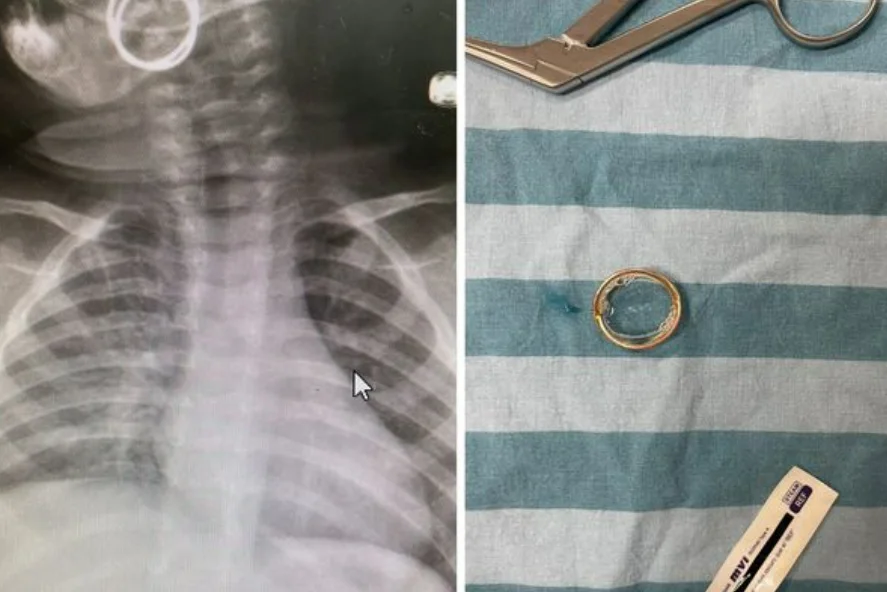

תינוק בן תשעה חודשים הובהל לחדר הלם במלר"ד בית חולים סבן לילדים בסורוקה, לאחר שזמן קצר לפני כן בלע טבעת, כך לדברי אימו.

לאחר בדיקה של הצוות הרפואי בחדר ההלם נמצא הגוף הזר בתוך הלוע של התינוק, ונשלף החוצה על ידי ד"ר יותם אייליג, רופא במחלקה לאף אוזן גרון - באמצעות פינצטה.

בתום השגחה המיון, שוחרר הפעוט לביתו כשמצבו טוב.